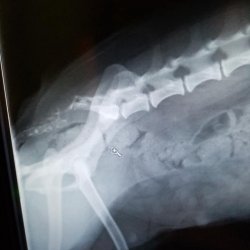

Ruby je velmi zanedbaná malá fenečka odebraná z nevhodných podmínek z Ústí. Olysalá místa na kůži měla způsobená zablešením a hormonální poruchou. Dostala speciální šampon a byla jí odebrána krev. Vzhledem k tomu, že Ruby nepoužívala ocas, který byl nehybný, zespodu odřený a ušpiněný od výkalů a moči, provedl se RTG snímek pánve, kde se ukázalo, že Ruby má ocas odtržený od pánve. Patrně po údajné autonehodě, nebo jiném úrazu v minulosti.

RTG snímek Ruby